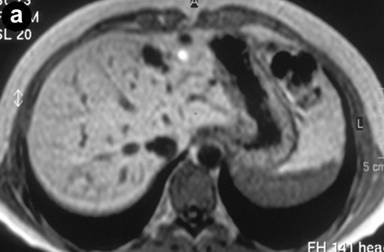

A 27-year-old female underwent a cholecystectomy for lithiasis. The patient was successively evaluated for diffuse and recurrent abdominal pain; no alcohol and/or smoking habits were reported. Laboratory measurements of total bilirubin and pancreatic amylases were unremarkable. Abdominal ultrasound was carried out which showed multiple hepatic and pancreatic cystic lesions; a dynamic enhanced CT scan confirmed the presence of multiple liver and pancreatic cystic lesions, but, in particular, the differentiation between simple hepatic cysts and cystic ectasia of the biliary ducts suggestive of Caroli’s disease was not reached. Therefore, MRI was requested to characterize the liver lesions and it was performed acquiring T1- and T2-weighted sequences integrated with T2-hydrographic images to specifically evaluate the biliary tract in axial and coronal views. MR cholangiography after intravenous administration of mangafodipir trisodium (Teslascan®, Nycomed, Amersham, Oslo, Norway), was also performed using T1-weighted sequences. Turbo spin echo T2-weighted images in axial and coronal views showed multiple hyperintense focal lesions in the left lobe of the liver, typical of cystic lesions, as well as multiple pancreatic cysts of the tail and saccular ectasia of the main biliary duct (Figure 1). T2-hydrographic dedicated images confirmed these findings, but certain imaging signs for a differential diagnosis between simple hepatic cysts and biliary cysts were not identified (Figure 2). However, the enhanced mangafodipir trisodium T1-weighted MRI clearly showed that some of the liver cysts concentrated mangafodipir trisodium contrast medium, thus demonstrating that these enhanced cystic lesions were in communication with the biliary ducts providing imaging criteria consistent with a diagnosis of Caroli’s disease (Figure 3). A segmental hepatectomy specimen demonstrated dilated simil-cystic intrahepatic ducts of the IV segment corresponding to a diagnosis of Caroli’s disease.

Figure 1. Conventional turbo spin echo T2-weighted axial (a., b. and c.) and coronal (d.) MR views show multiple cystic lesions in the left liver lobe as well as in the pancreatic tail. Saccular ectasia of the main biliary duct is also depicted. |